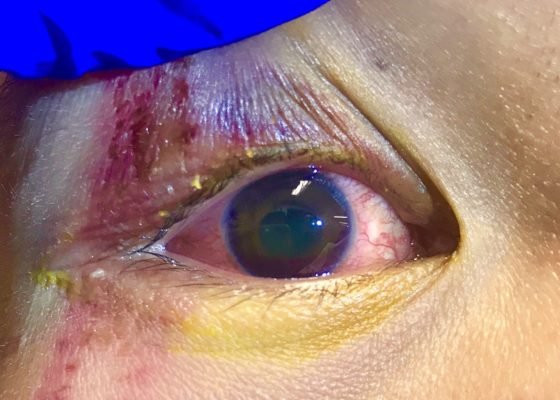

Raynaud’s Phenomenon

Photograph contributed by Richard Saunders, DO, FACEP Keywords: Raynaud’s phenomenon, Raynaud’s syndrome.